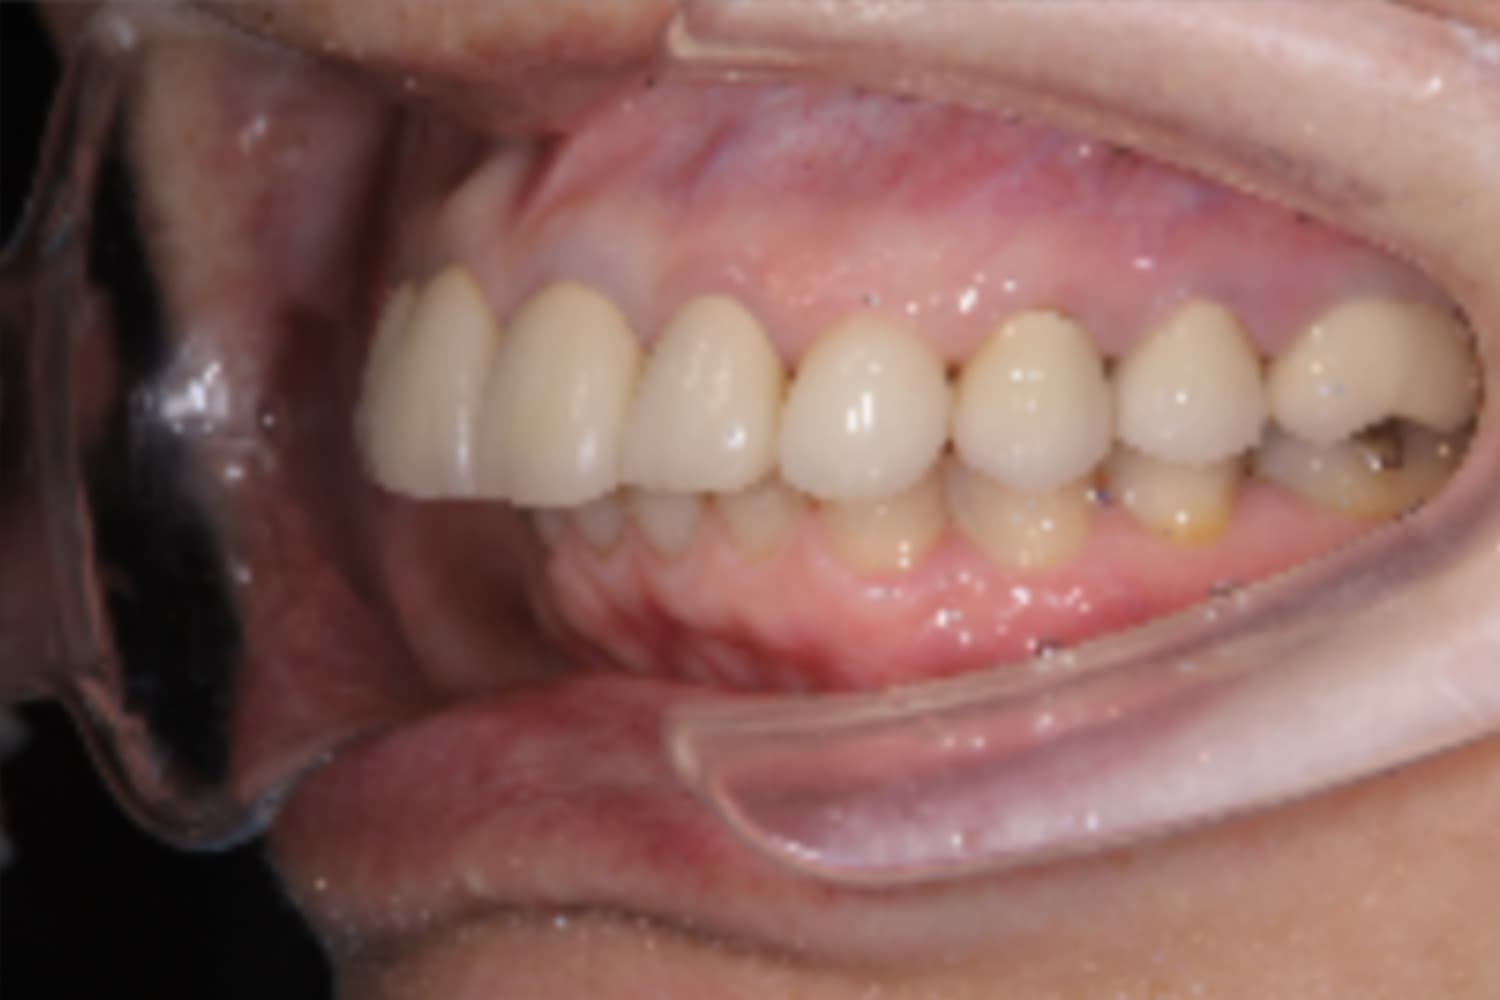

左上犬歯のインプラント治療

Before

After

抜歯と同時にインプラント治療を行いました。

主訴

左上犬歯の被せ物の脱離

治療期間

6カ月

治療回数

8回

費用

533,500円

副作用・リスク

・抜歯後即時にインプラントを埋入するため、結合不良リスクが高いです。 ・結合不良の場合、インプラント再埋入など追加処置が必要となります。